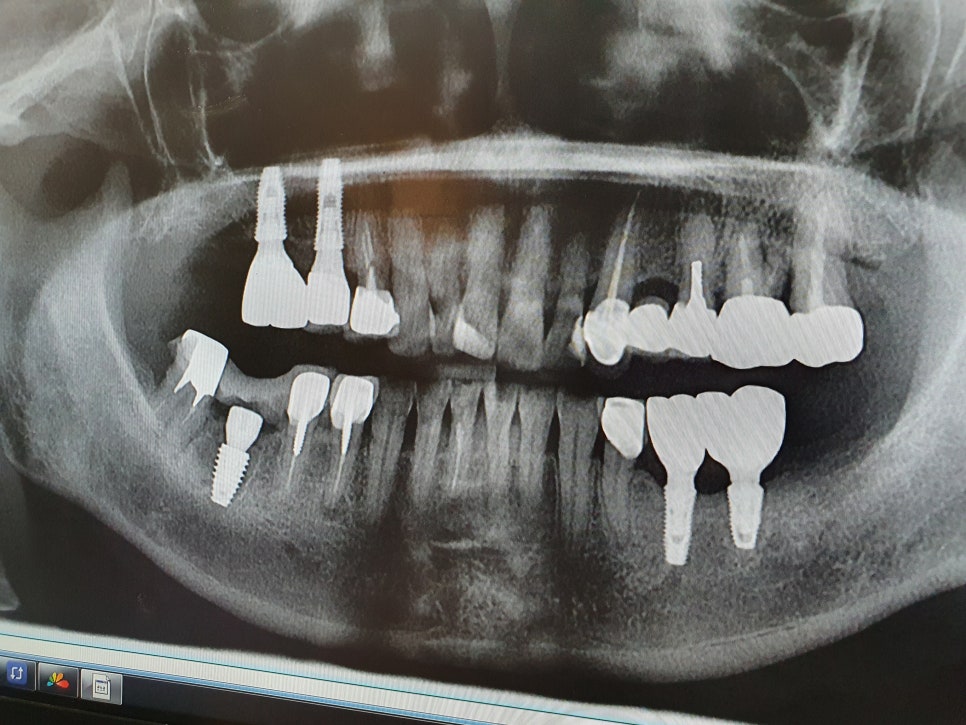

임플란트 식립때 사용되는 Kit